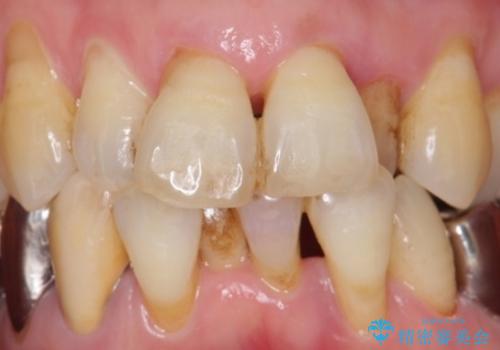

- 下の前歯(左下2)と奥歯の動揺がひどくなってきたことを主訴に来院された患者様です。

精査したところ、前歯の咬み合わせが反対になっていること、下の奥歯(下顎両側67)が4本欠損していることから動揺が生じていました。

入れ歯も抵抗があるとのことから、相談を重ね、今の状態では保存不可能な下の前歯(左下2)を抜去し、ブリッジや連結補綴により動揺を抑えることにしました。

また、咬み合わせが反対になっている上の前歯(左上2)も補綴で形を変えることにより、咬合を改善しました。